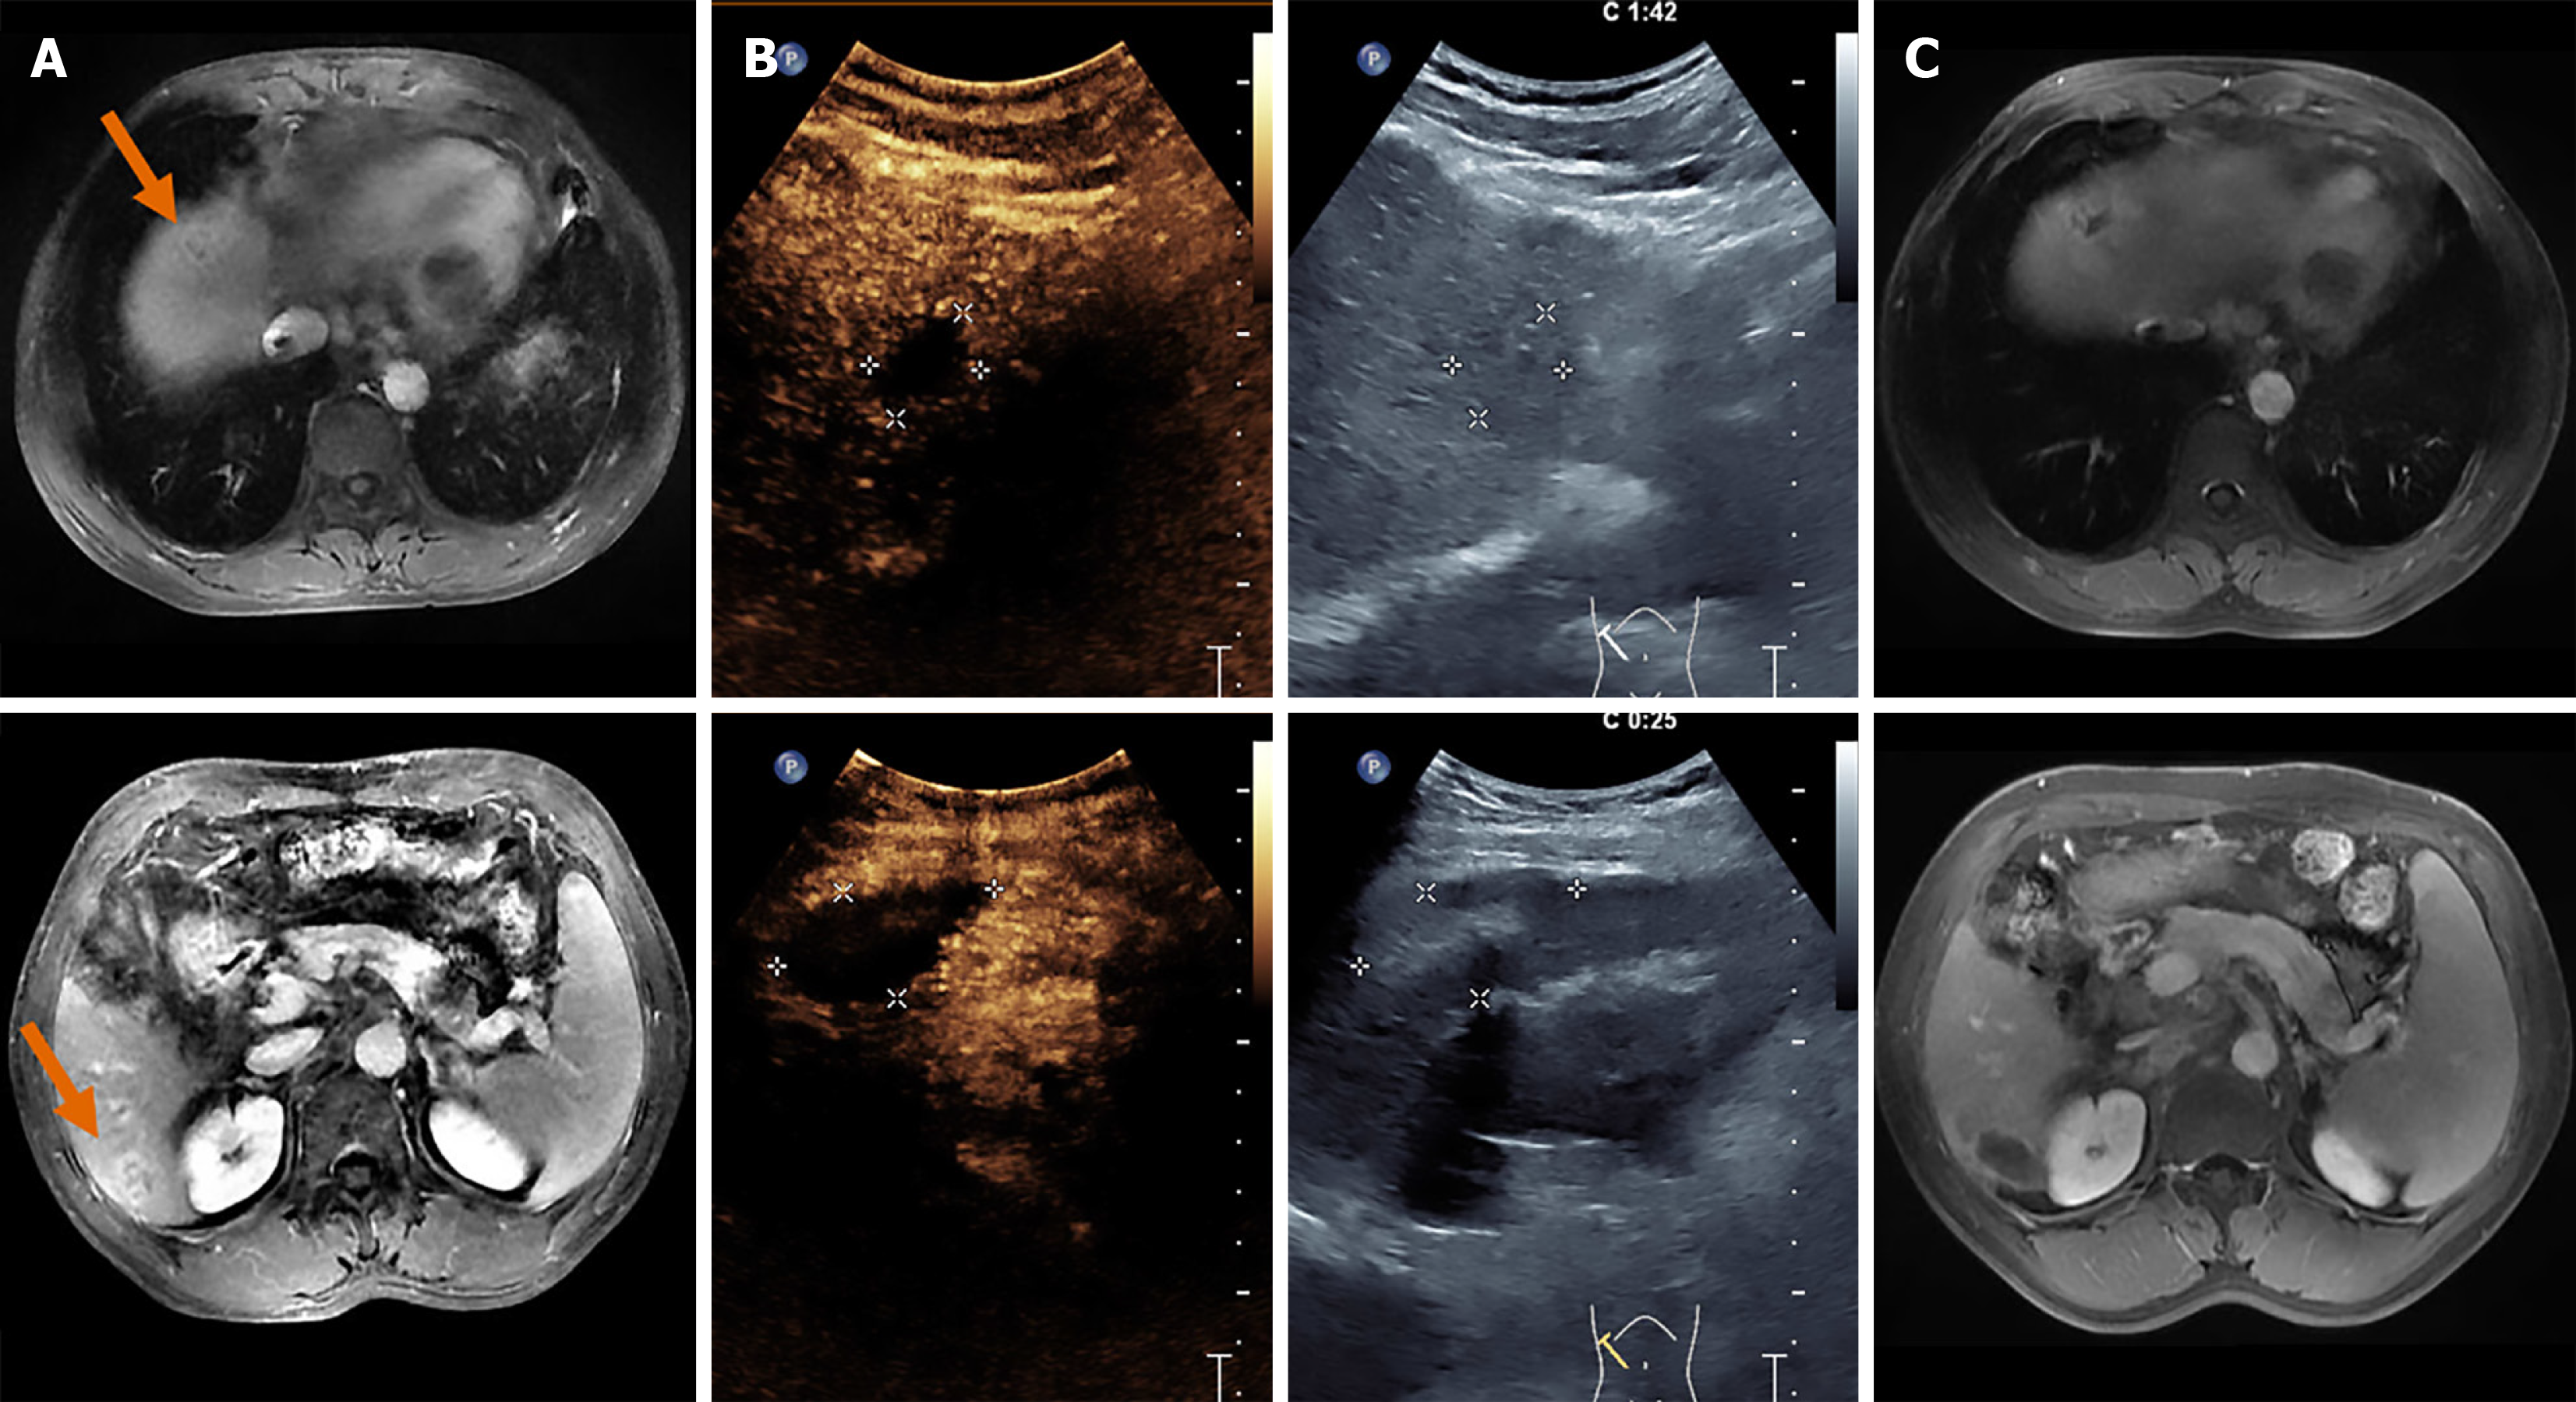

Figure 2 Single-session ablation: A 62-year-old male underwent successful ablation of two colorectal liver metastases in liver segments S4 and S6 during a single-session ablation procedure.

A: Pre-ablation imaging (orange arrows point to the target lesion); B: Intraoperative contrast-enhanced ultrasound; C: Post-ablation imaging.